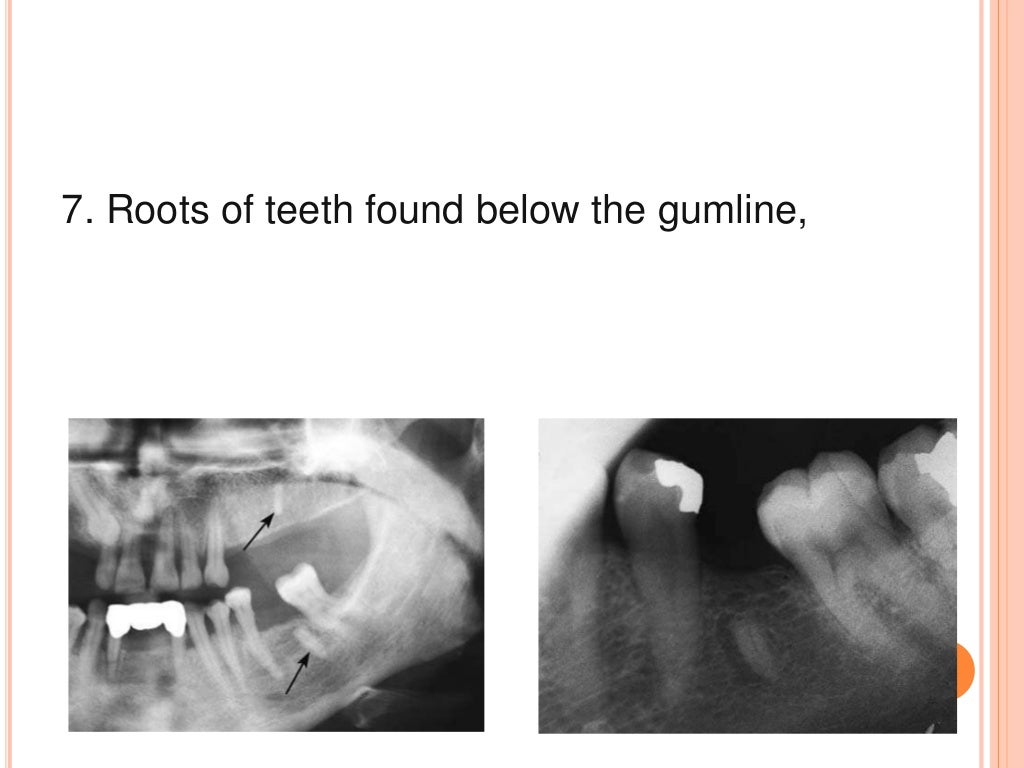

Surgical Tooth Extraction Procedure Steps . A cut is made in the. A simple extraction involves a tooth that is visible above the gums. having a tooth removed is a surgical procedure and as such carries a few risks. Your dentist will administer the anesthetic to the immediate area around the tooth. here are the general steps of tooth extraction: Here are some of the common reasons why teeth are removed: dental surgeons may classify extractions as simple or surgical. Your dentist will release the tooth from the fibers connecting it to the bone. the stages of surgical removal of teeth or roots of teeth commonly include: surgical tooth extraction is simply the first step on the road to improved oral health. Do i need an oral surgeon to remove a tooth? it’s never fun hearing that you need to have a tooth pulled. While simple tooth extractions can occur in a general dentist’s office, patients with impacted wisdom teeth or severely damaged or decaying teeth require surgical tooth removal by an oms. But sometimes, a tooth extraction is the best way to eliminate. Once loosened, the tooth is elevated from the socket.